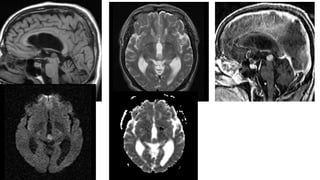

MRI Findings

• T1W Heterogeneous intensity-(high signal from fat)

• T2W Soft tissue is iso- hyperintense .

• T1W+C soft tissue component enhancement

• Fat suppressed imaging (Recommended) Signal drop out in the fatty

component

• #22 Axial CT image showing heterogenous pineal mass contain(arroehead), soft tissue and calfications.Coronal T2W and axial T1W+C showing enhancing soft tissue component of the teratoma (arrow head).

• #23 Pineal teratoma in a 2-year-old boy. Axial (a) and sagittal (b) T1-weighted MR images show a large, heterogeneous pineal gland mass (arrowheads) and severe obstructive hydrocephalus.